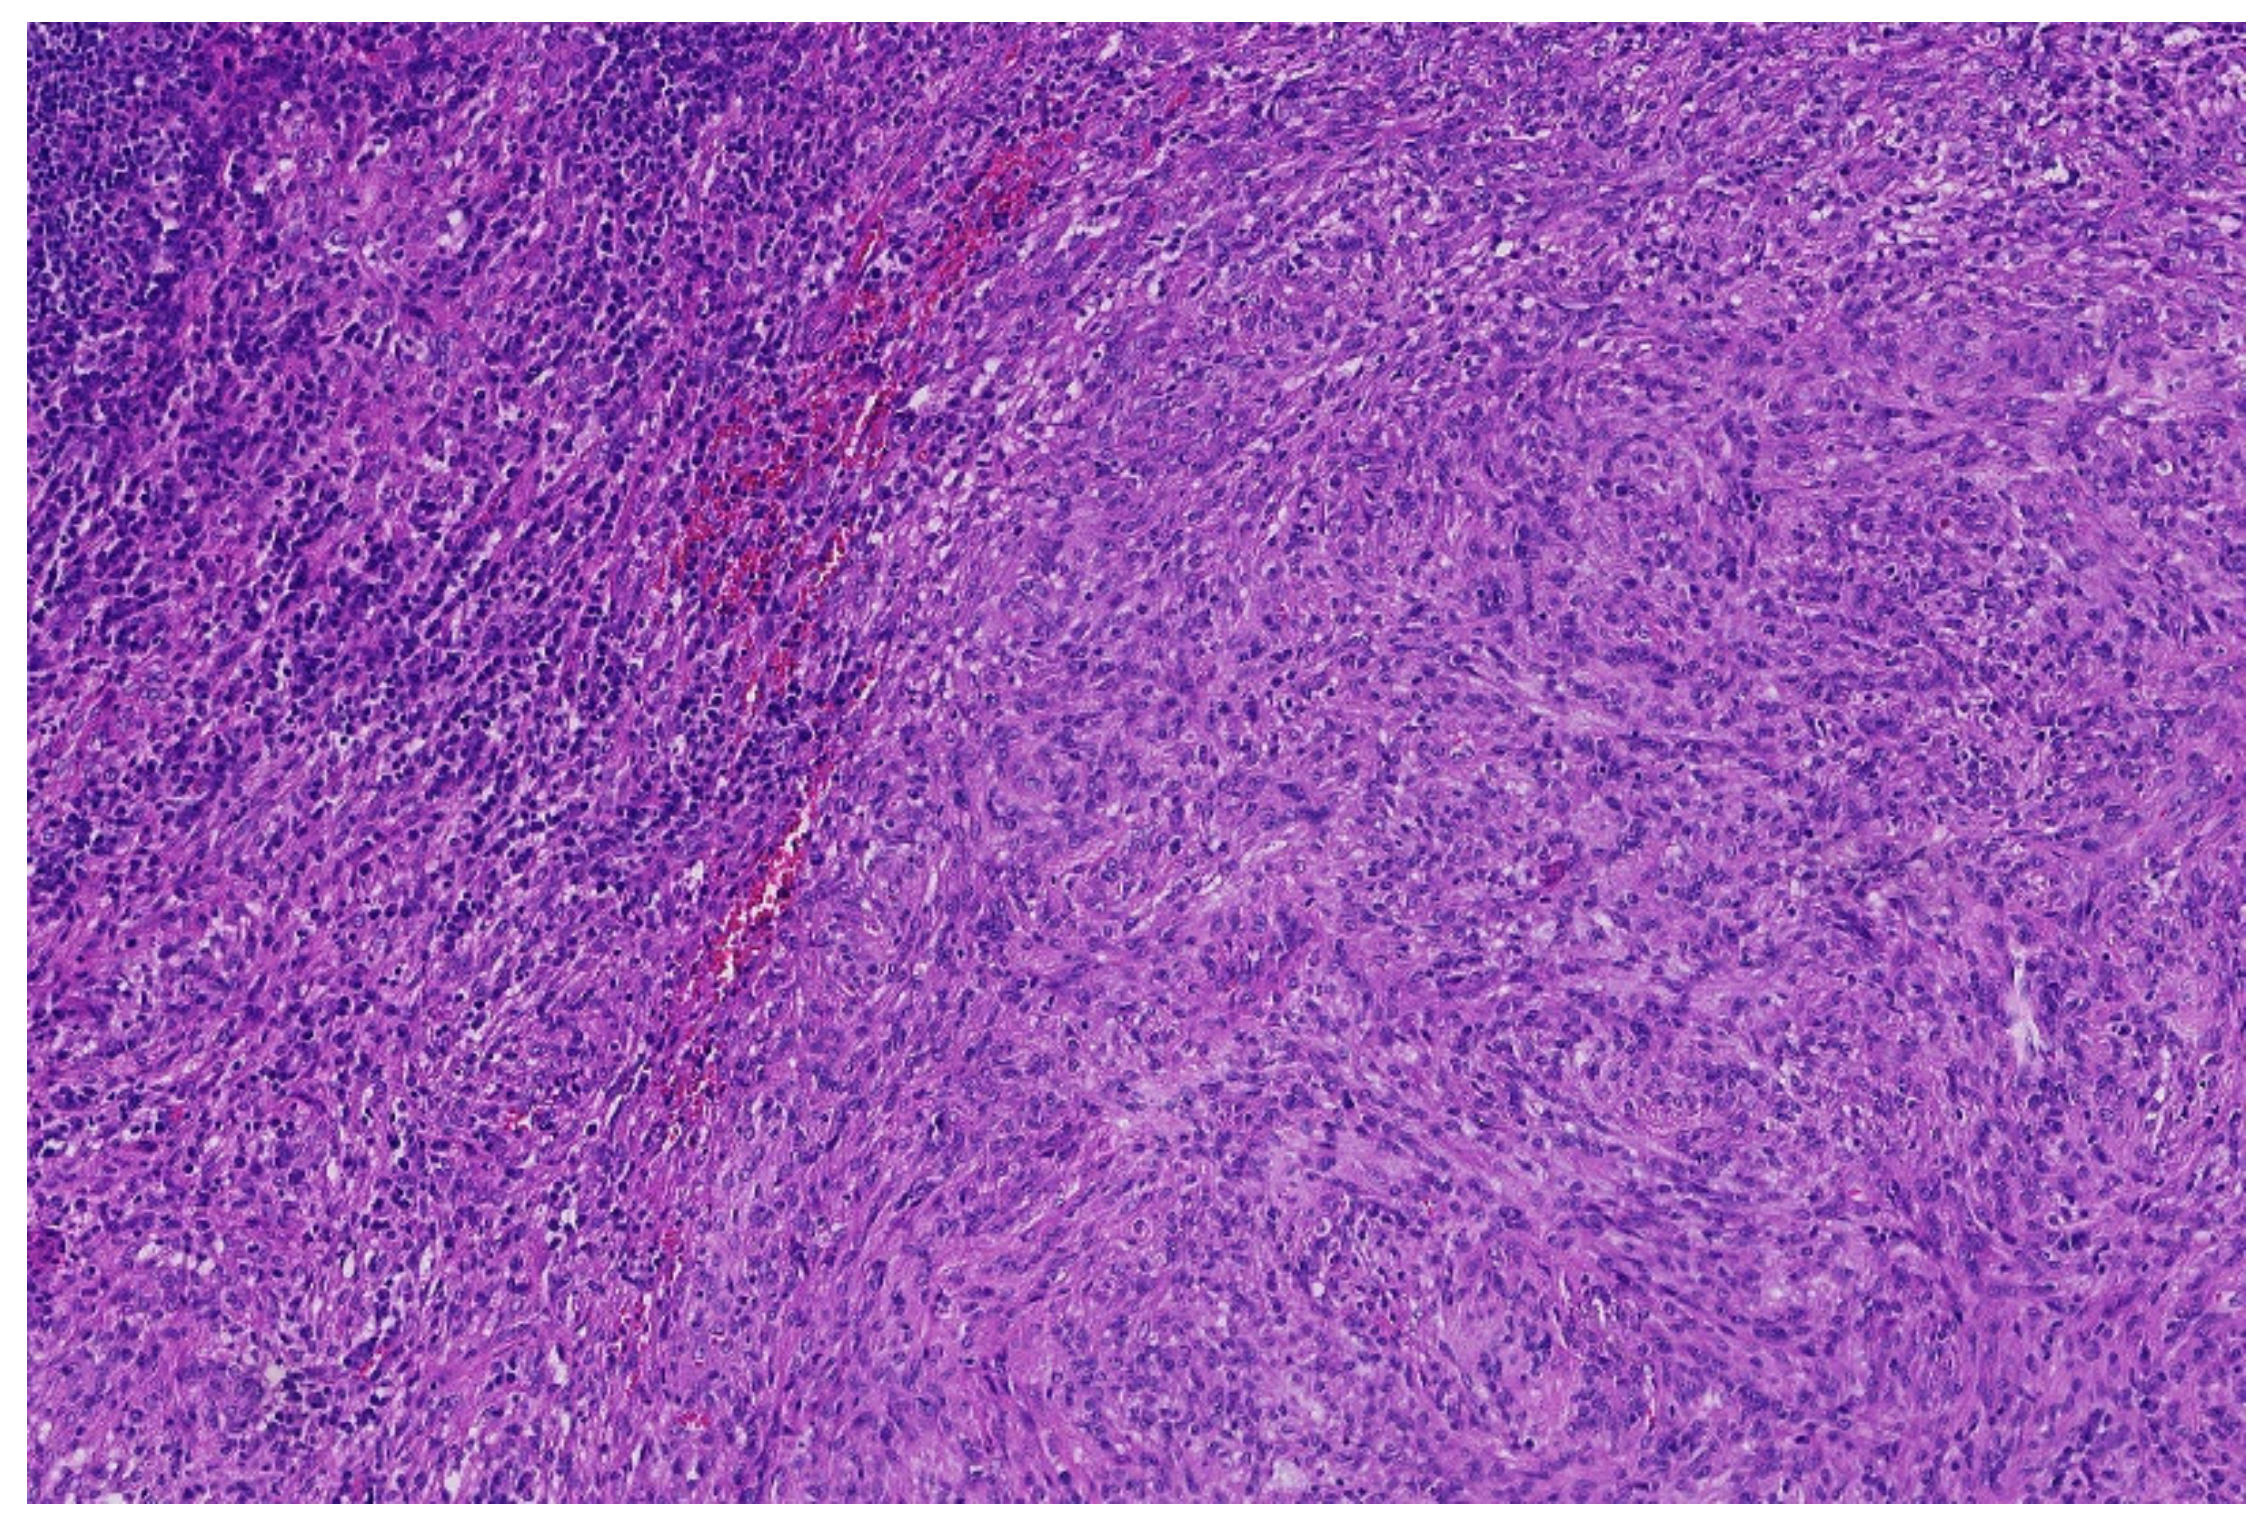

2. Ewing Sarcoma

3.4. Desmoplastic Small Round-Cell Tumor (DSCRT)